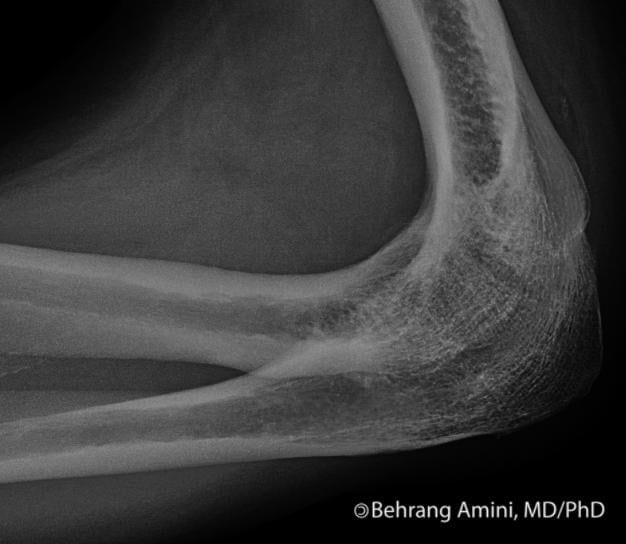

Для диагностирования заболевания используются инструментальные методы: рентгенография, КТ, МРТ. Консервативное лечение анкилоза не проводится. Оперативное вмешательство (остеотомия, артропластика, эндопротезирование сустава) показано пациентам при патологии в функционально неблагоприятном положении. После диагностирования анкилоза коленного, плечевого, тазобедренного суставов больному дают группу инвалидности.

Анкилоз коленного, плечевого, тазобедренного суставов выявляется при проведении инструментальных исследований по сужению и прерывистым контурам суставной щели или ее полному сращению. При диагностировании используются:

- рентгенография;

- компьютерная томография;

- магнитно-резонансная томография.

Хрящевой и костный анкилоз тазобедренного, локтевого суставов, голеностопа с помощью консервативных методов вылечить не удастся из-за необратимых изменений в суставных структурах. Проводится хирургическая операция — артропластика. Сращенные кости разъединяются с дальнейшим восстановлением их поверхностей и размещением между ними прокладок для предупреждения истирания. Если сустав закостенел в функционально порочном положении, показана остеотомия для выпрямления пораженной конечности. При осложненном анкилозе проводится эндопротезирование — полная замена коленного, тазобедренного, голеностопного суставов.